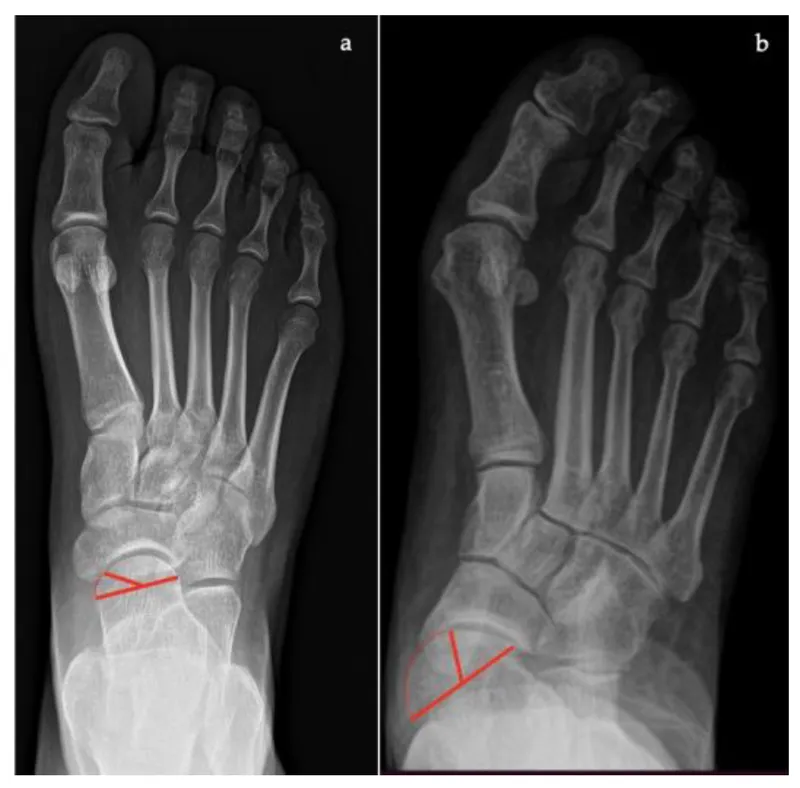

The hallux valgus algorithm demonstrates evidence-based decision-making. Mild deformities (HVA <30°, IMA <13°) achieve 95% satisfaction with distal osteotomies. Severe deformities (HVA >40°, IMA >20°) require proximal procedures to prevent recurrence rates >40%.

📌 Remember: "MILD, MODERATE, SEVERE" for hallux valgus surgery - Metatarsal head procedures (HVA <30°), Intermediate shaft osteotomies (HVA 30-40°), Lapidus fusion (HVA >40°), Double procedures for severe cases. Recurrence rates increase exponentially with inappropriate procedure selection.

📌 Remember: "ANGLES" for critical measurements - Anterior distal tibial angle (93±2°), Normal calcaneal pitch (20-30°), Great toe hallux valgus (<15°), Lateral distal metatarsal angle (<8°), Expected correction (70-80% of deformity), Subtalar motion (30° inversion, 15° eversion)